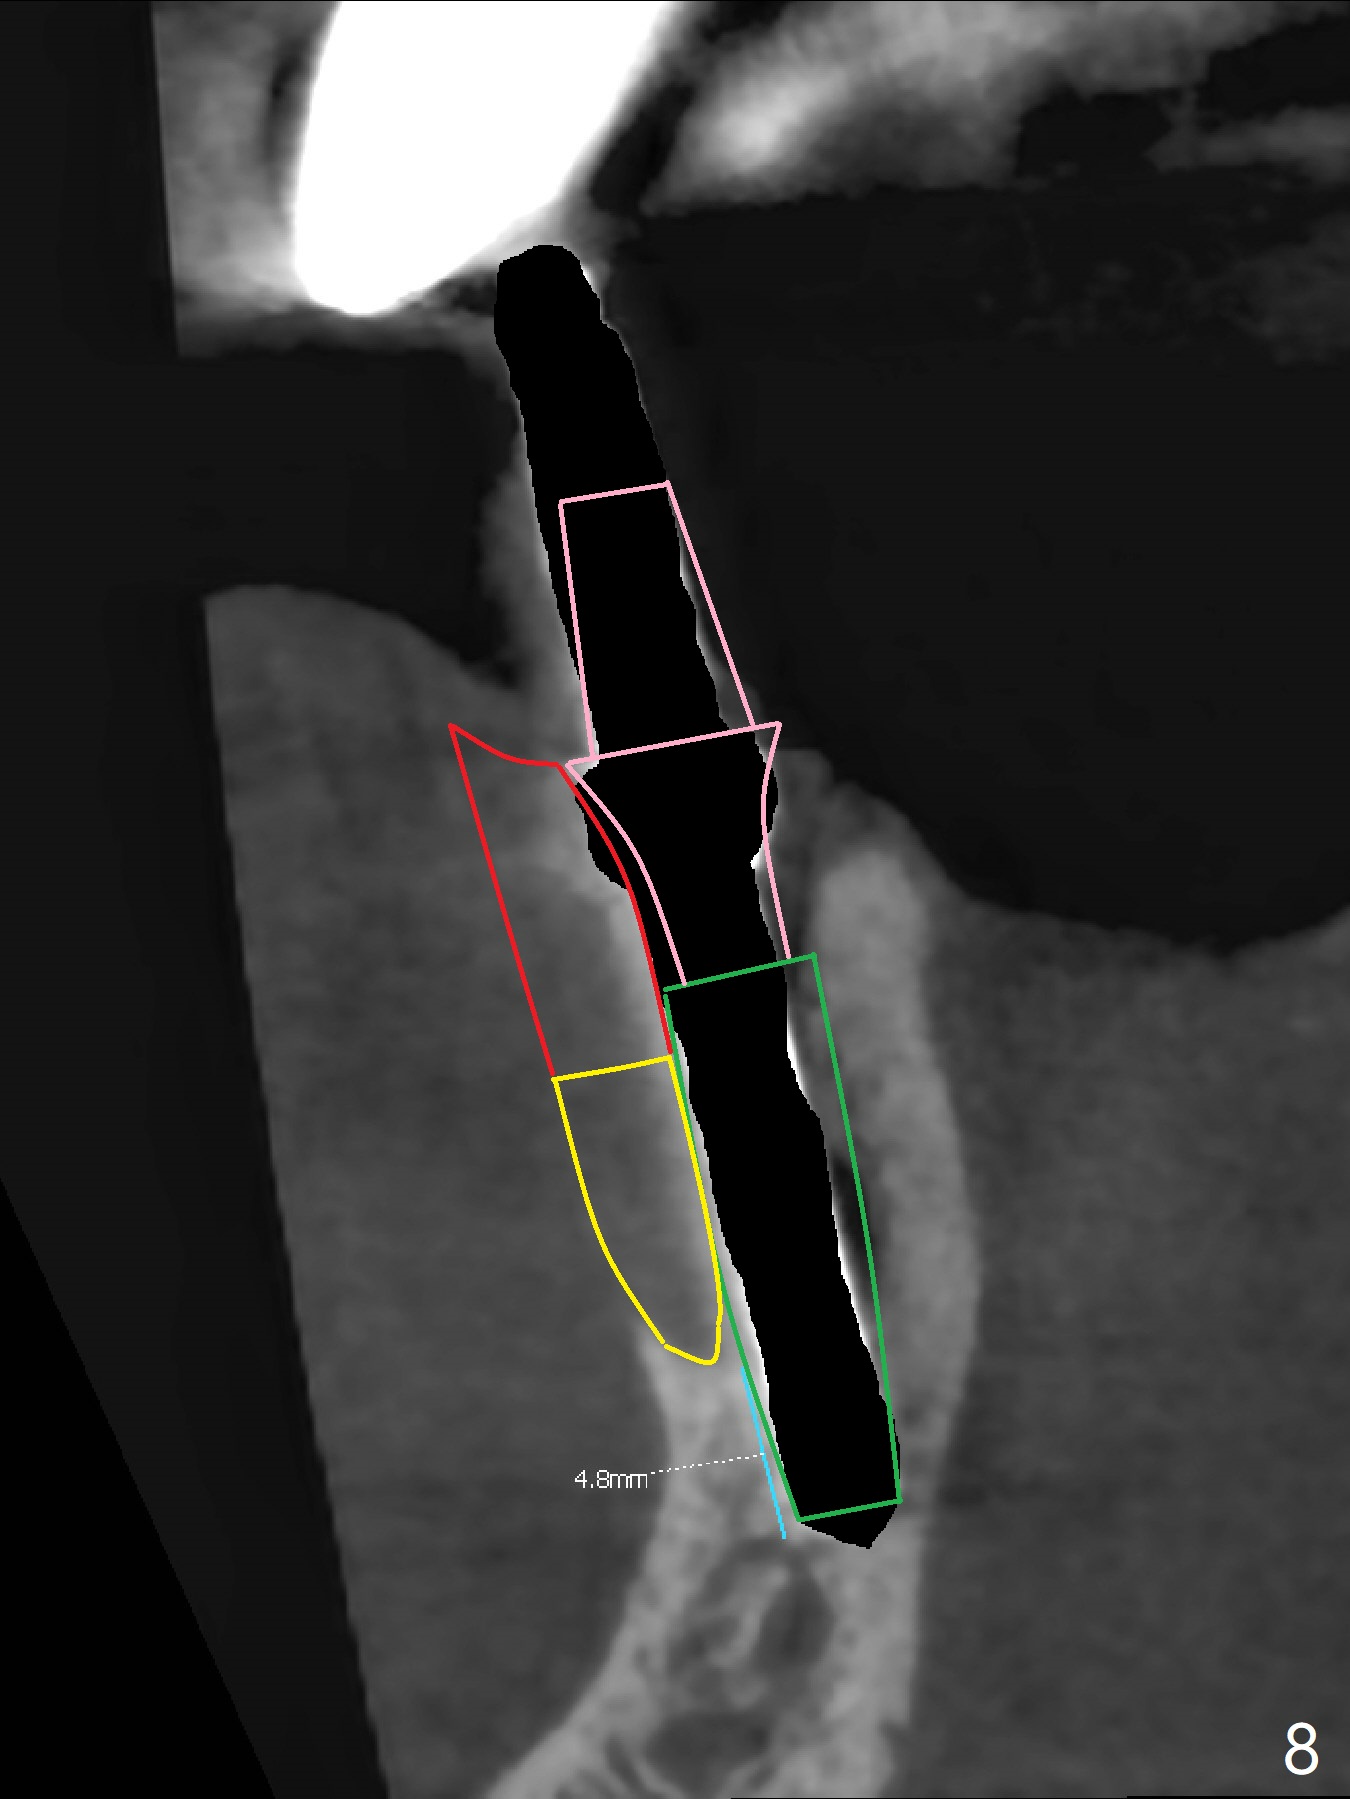

After removal of the split residual roots at #22 (Fig.1), the buccal wall is found to be defective, while the coronal portion of the lingual one (Fig.2 L) is confirmed to be more buccal than the apical portion. A vertical slot is made in the coronal portion of the lingual plate (Fig.3 *) in order to establish osteotomy lingual (Fig.4 O). The depth of the osteotomy in the apical native bone is 4.8 mm (Fig.5 CT coronal section). After the final drill (3 mm) is removed, a 3.8x16 mm implant is placed lingually for secure 2-pointed fixation (Fig.6,7, coronally: mesiolinguodistal; apically: in the native bone (Fig.9)). The essence of the lingual placement is the presence of a large buccal gap for Osteogen plug (Fig.8 yellow) and allograft (Fig.8 red, 9,10 (*)) for potential regeneration of the buccal plate. With bone graft and the overlying provisional (Fig.11 P), the buccal plate seems to have been established (*) 1 week postop. There is no obvious implant thread exposure 8 months postop (Fig.12). But the buccal plate is atrophic when the crown is cemented (~10 months postop, Fig.13).